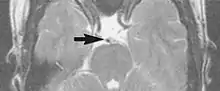

Flow can manifest as either an altered intravascular signal (flow enhancement or flow-related signal loss), or as flow-related artifacts (ghost images or spatial misregistration). Flow enhancement, also known as inflow effect, is caused by fully magnetised protons entering the imaged slice while the stationary protons have not fully regained their magnetization.[1] The fully magnetized protons yield a high signal in comparison with the rest of the surroundings. High velocity flow causes the protons entering the image to be removed from it by the time the 180-degree pulse is administered. The effect is that these protons do not contribute to the echo and are registered as a signal void or flow-related signal loss (Fig. 2).[1] Spatial misregistration manifests as displacement of an intravascular signal owing to position encoding of a voxel in the phase direction preceding frequency encoding by time TE/2.The intensity of the artifact is dependent on the signal intensity from the vessel, and is less apparent with increased TE.[1]